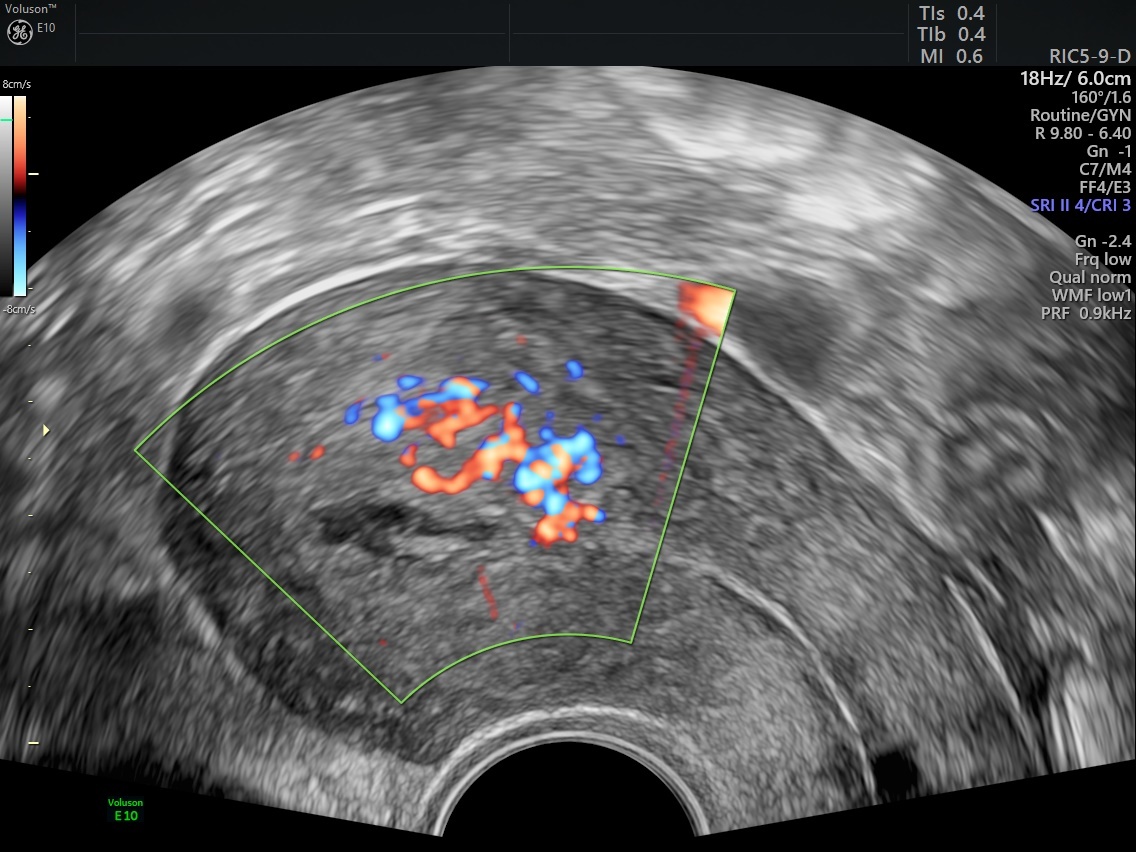

From www.volusonclub.net

How Retained Products of Conception Can Impact Fertility Empowered Women's Health What Do Retained Products Of Conception Look Like Retained products of conception (rpoc) refer to the persistence of placental and/or fetal tissue in the uterus following delivery, termination of pregnancy or a miscarriage. Retained products of conception (pocs) can occur after spontaneous or induced abortion and after delivery. Retained products of conception (rpoc) generally result after first half of pregnancy termination and also may occur after vaginal or. What Do Retained Products Of Conception Look Like.